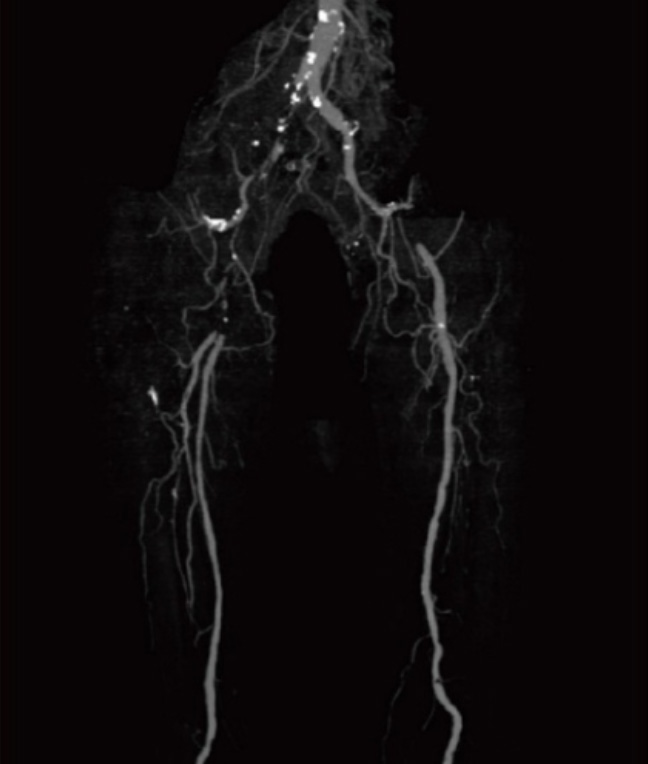

閉塞性動脈硬化症

閉塞性動脈硬化症とは足に血液や栄養を送る動脈(下肢動脈)で動脈硬化が進行し、血管が狭くなったり詰まったりすることで、足への血流が悪くなり、さまざまな症状を引き起こす病気です。

出典:インフォームドコンセントのための心臓・血管病アトラス

【主な症状】

初期には、足の「しびれ」や「冷え」を感じることがあります。

病気が進行すると、「間欠性跛行(かんけつせいはこう)」と呼ばれる特徴的な症状が現れます。これは、「少し歩くと足に痛みや疲れを感じて休みたくなる」「休むと痛みが治まり、また歩けるようになる」という状態を繰り返すものです。

〈このような症状はありませんか?〉

・足が冷たい、しびれる

・歩くと足がすぐ疲れる、痛くなる

・足の色が赤黒い・紫がかっている・黒い

・足の傷がなかなか治らない

早期発見・早期治療が大切です。閉塞性動脈硬化症は、早期に発見して治療を行えば、進行を食い止めることが可能です。症状が進んでからでは、治療の選択肢が限られ、生活の質が大きく損なわれることもあります。 気になる症状がありましたら、お気軽に当院にご相談ください。専門の医師が丁寧に診察・治療いたします。